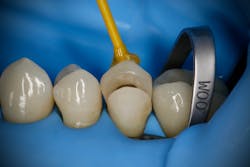

While performing esthetic dentistry, our bonding materials must work as promised to achieve long-term success.2 When manufacturers report bond strengths in the clinical arena, studies are conducted with the rubber dam in place (figures 1 and 2). When etched surfaces are exposed to the oral environment, including expired air while using typical isolation devices, the surfaces are challenged by moisture from numerous sources, causing the adhesive chemistry to be altered. Hence, to achieve the best bond strengths, a well-sealed barrier will help our results, often dramatically.